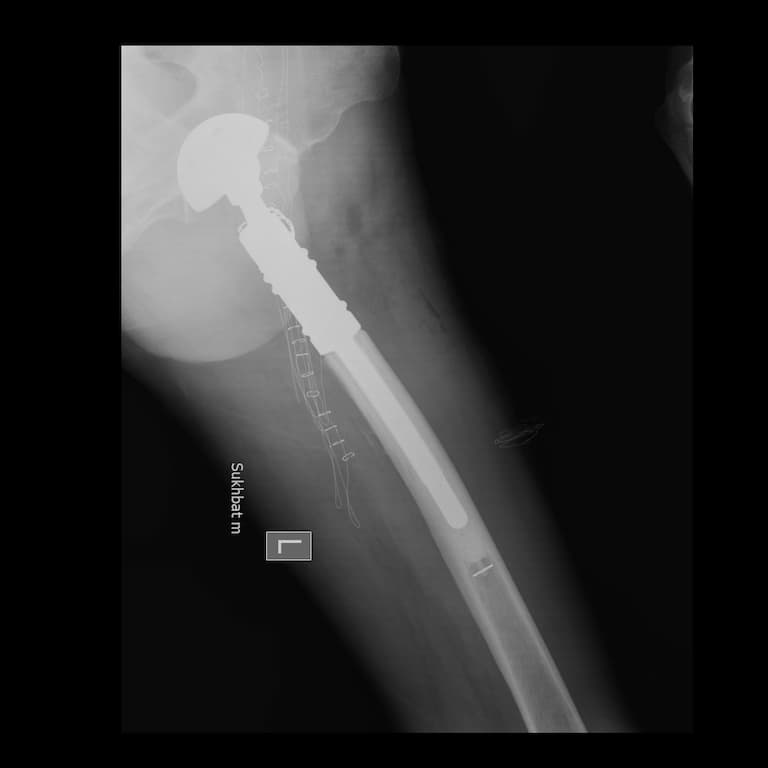

Дунд чөмөгний дээд хэсгийн /проксималь/ хавдар

Дунд чөмөгний проксималь буюу дээд хэсгийг хамарсан яс, зөөлөн эдийн гаралтай хавдрын улмаас түнхний үе, дунд чөмөгний дээд хэсгийг бүхлээр нь солих (мөч хадгалах мэс засал) мэс заслын эмчилгээг хийнэ.

Мэс заслын өмнөх болон дараах рентген зураг

Түнхний үе солих мэс засал гэж юу вэ image8Түнхний үе солих мэс засал гэж юу вэ image9Түнхний үе солих мэс засал гэж юу вэ image10